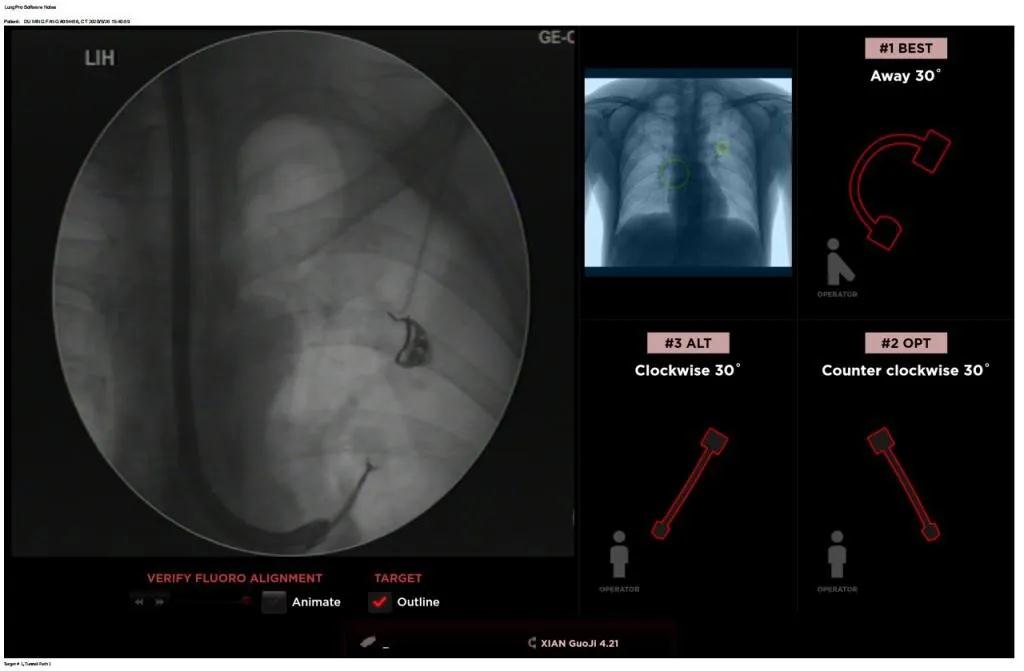

近日,西安國際醫(yī)學(xué)中心醫(yī)院胸科醫(yī)院歐陽海峰副院長完成西北地區(qū)首例LungPro全肺導(dǎo)航系統(tǒng)引導(dǎo)下經(jīng)支氣管鏡跨肺實(shí)質(zhì)肺外周結(jié)節(jié)活檢術(shù)。

經(jīng)過充分的討論后,歐陽海峰副院長決定為患者實(shí)施LungPro全肺導(dǎo)航系統(tǒng)引導(dǎo)的經(jīng)支氣管跨肺實(shí)質(zhì)肺外周結(jié)節(jié)活檢術(shù)。Broncus導(dǎo)航系統(tǒng)LungPro具有全球領(lǐng)先獨(dú)創(chuàng)的BTPNA技術(shù)(支氣管鏡下跨結(jié)節(jié)抵達(dá)術(shù)),可以實(shí)現(xiàn)對氣道外周孤立性肺小結(jié)節(jié)的精準(zhǔn)定位,建立直接通往氣道外病變部位的通道,以實(shí)現(xiàn)全肺的診斷及后續(xù)治療。這項(xiàng)技術(shù)不僅彌補(bǔ)了現(xiàn)有支氣管鏡技術(shù)由于受限于病變部位是否有氣道可通向以及無法準(zhǔn)確定位病變部位而造成的較低診斷率,同時還彌補(bǔ)了CT引導(dǎo)下經(jīng)胸穿刺(TTNA)無法適用于某些特定部位如中央及肩胛骨等結(jié)節(jié)的問題,并且還避免了經(jīng)胸穿刺給患者帶來氣胸、出血的高風(fēng)險,可有效提高肺部結(jié)節(jié)及早期肺癌診斷陽性率,亦可用于早期肺癌的射頻消融或微波治療,具有微創(chuàng)、安全、同期雙肺診療等優(yōu)勢。

團(tuán)隊(duì)術(shù)前進(jìn)行了精心的準(zhǔn)備,通過高分辨率CT建立了導(dǎo)航路徑,在麻醉科手術(shù)室的配合下,借助LungPro引導(dǎo)順利的確定了病灶部位、建立隧道并實(shí)施活檢,術(shù)后患者恢復(fù)順利出院。